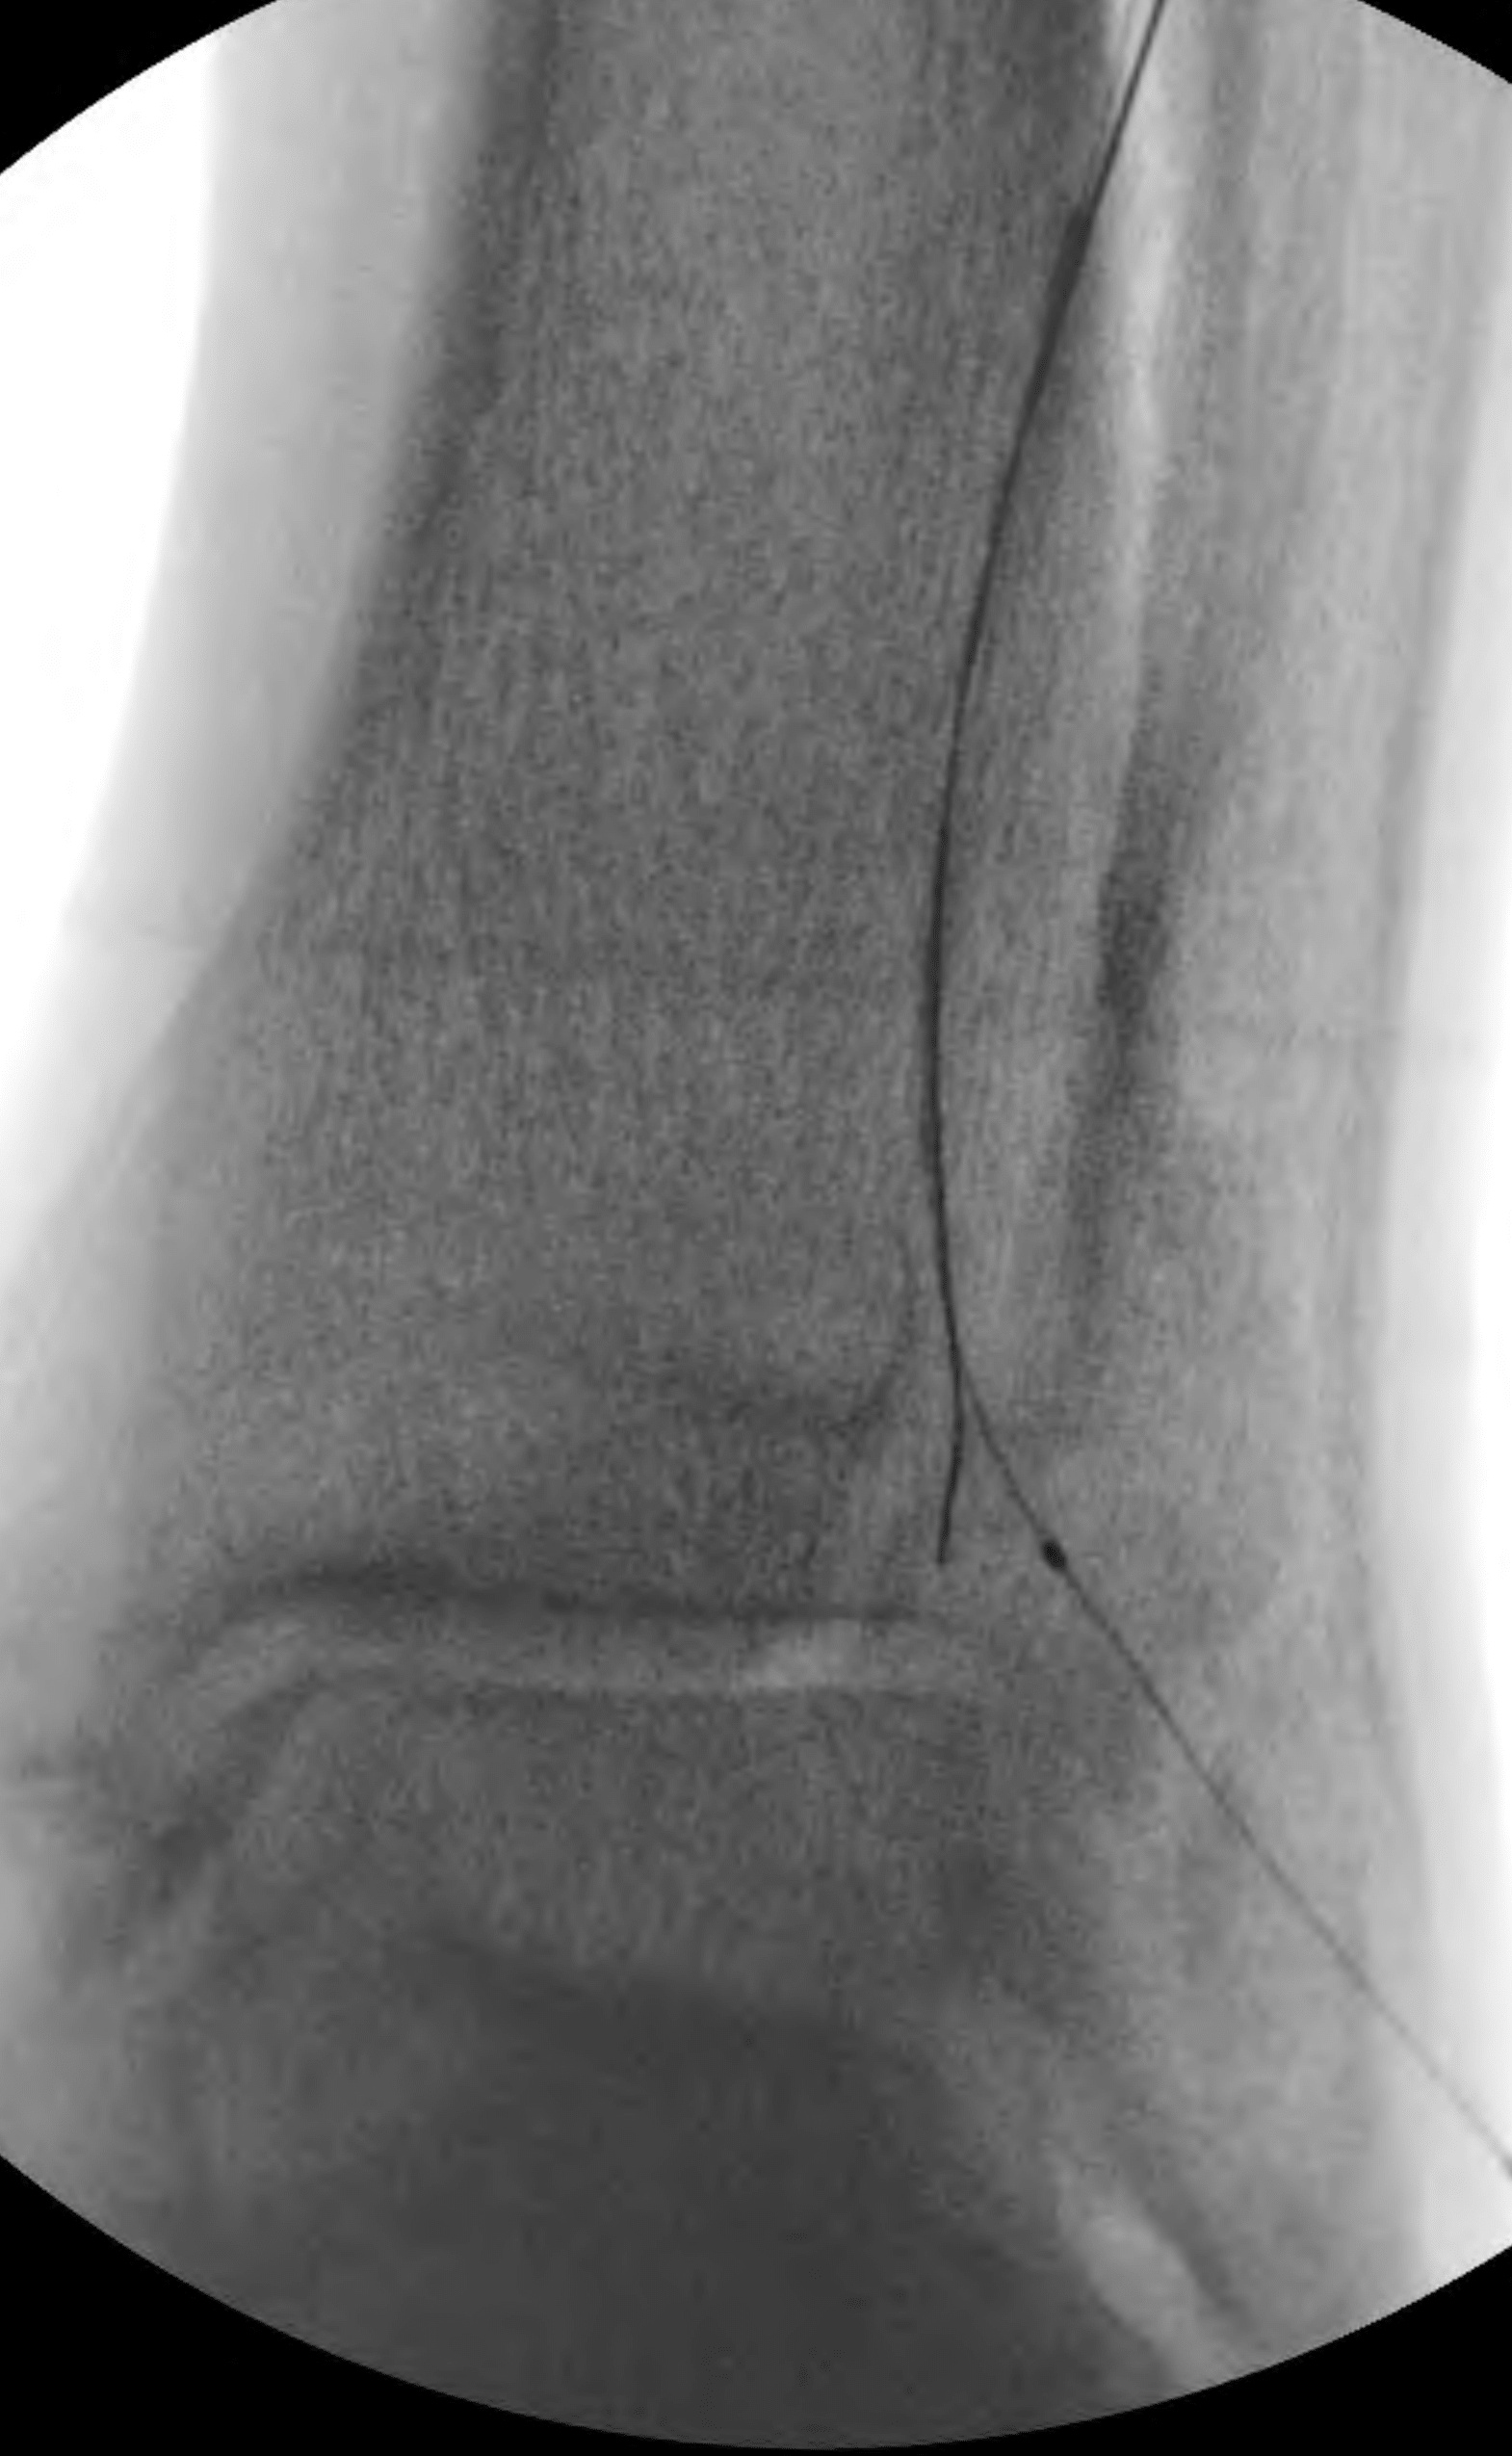

The anterior tibial artery was chosen as the target of revascularization given the predominant supply to the forefoot via the dorsalis pedis artery compared with the lesser supply via the diminutive plantar arteries. An “up and over” approach from a contralateral right common femoral artery access was successful in crossing to the distal segment of the anterior tibial artery in antegrade fashion; however, further crossing could not be achieved in antegrade fashion (Figure 5).

In order to cross and treat the remainder of the distal anterior tibial artery occlusion, a retrograde pedal access was desired. Due to concerns about puncture-related injury to the dorsalis pedis artery that could potentially compromise the patient’s existing flow as well as a potential surgical bypass target, retrograde pedal access of the patent dorsalis pedis artery was avoided at this point. Instead, a plan was made to obtain retrograde pedal access of the occluded segment of the distal anterior tibial artery above the reconstitution point (Figure 6).